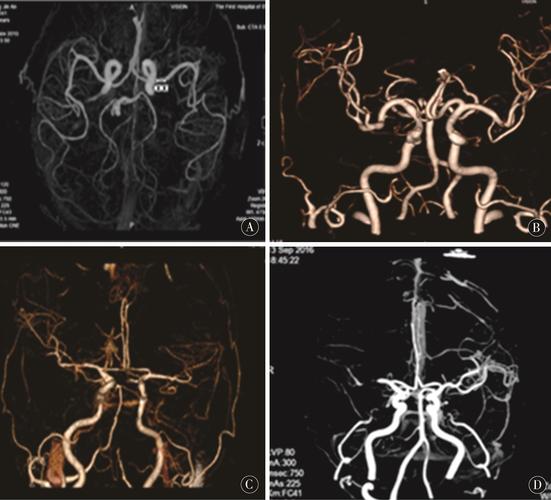

(图片来源网络,侵删)